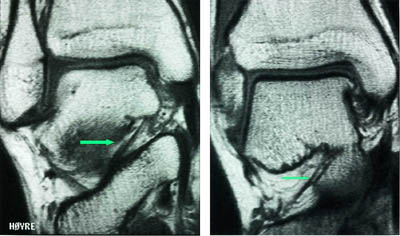

Mesteparten av sinus tarsi er fylt med fett. Dette gir høysignal på T1-vektet sekvensog lavsignal på fettsuppresjonssekvenser. Blodkar og nervefibrer gir små punktformige lavsignaler medialt i fettvevet på T1-vektet sekvens. Ligamentene gir lavsignal på spinnekkosekvensene. Figur 1 viser en normal sinus tarsi. I koronalplanet sees ligamentum cervicale ventralt og ligamentum interosseus noe lenger dorsalt. Det mest fremtredende og hyppigste MR-funnet ved sinus tarsi-syndrom er lavsignalområder på T1-vektet sekvens og lav- eller høysignalområder på T2-vektet sekvens. Forandringene er forårsaket av fibrose (fig 2) med eller uten inflammasjon (fig 3). Av og til kan vi se små væskelokulamenter som representerer ganglioncyster (fig 4). Ligamentene kan være vanskelig å se, enten fordi det er mye inflammasjon eller fordi de er røket. Hos en del pasienter kan man finne ruptur av laterale ankelligamenter, spesielt ligamentum talofibulare anterior.

I tillegg til å kunne påvise patologiske forandringer i sinus tarsi kan vi påvise andre årsaker til smerter lateralt i bakfoten: Osteokondrale skader ved øvre laterale talushjørne, avaskulære nekroser og stressfrakturer i omliggende knokler samt patologi i omliggende ligamenter og sener (fig 5) og (fig 6).